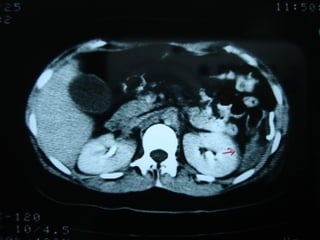

CASO 2

• Paciente varón, 35 años de edad,

víctima     de    accidente   de   tránsito

(peatón).

• RTS: 7,55       NISS: 27